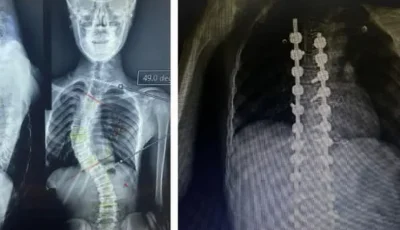

فريق طبي بجامعة بني سويف ينجح في إصلاح اعوجاج بالعمود الفقري لأحد المرضى

أعلن الدكتور طارق على ، القائم بأعمال رئيس جامعة بني سويف، نجاح فريق طبي بقسم جراحة المخ والأعصاب بكلية الطب في إصلاح اعوجاج في...